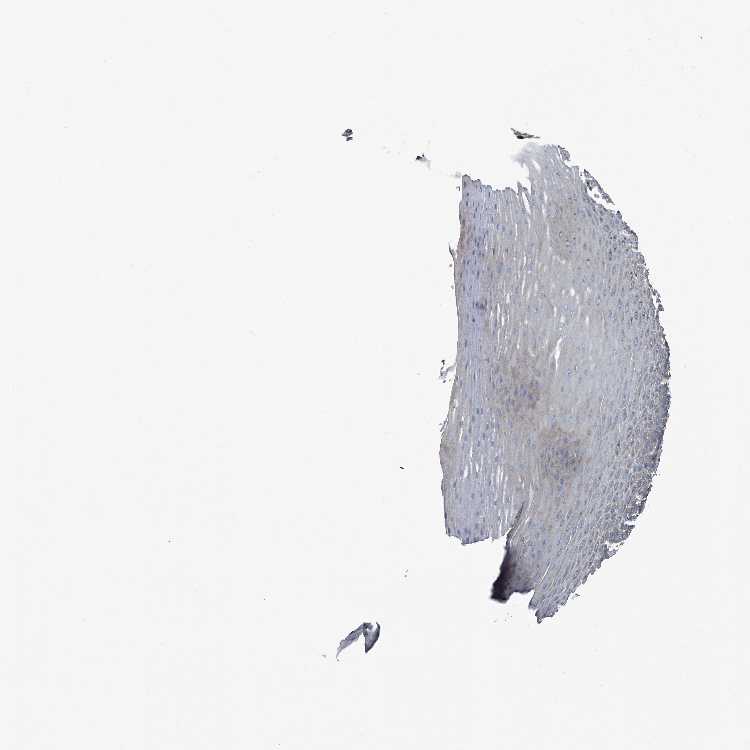

ESOPHAGUS - Antibody stainingi

Antibody staining in the annotated cell types in the current human tissue is reported as not detected, low, medium, or high, based on conventional immunohistochemistry profiling in selected tissues. This score is based on the combination of the staining intensity and fraction of stained cells.

Each image is clickable and will lead to virtual microscopy that enables deeper exploration of all samples and also displays staining intensity scores, fraction scores and subcellular localization as well as patient and tissue information for each sample.

Antibody HPA023309Antibody HPA029524

Squamous epithelial cells LowMedium